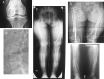

In children, hypophosphatemic rickets (HR) is revealed by delayed walking, waddling gait, leg bowing, enlarged cartilages, bone pain, craniostenosis, spontaneous dental abscesses, and growth failure. If undiagnosed during childhood, patients with hypophosphatemia present with bone and/or joint pain, fractures, mineralization defects such as osteomalacia, entesopathy, severe dental anomalies, hearing loss, and fatigue. Healing rickets is the initial endpoint of treatment in children. Therapy aims at counteracting consequences of FGF23 excess, i.e. oral phosphorus supplementation with multiple daily intakes to compensate for renal phosphate wasting and active vitamin D analogs (alfacalcidol or calcitriol) to counter the 1,25-diOH-vitamin D deficiency. Corrective surgeries for residual leg bowing at the end of growth are occasionally performed. In absence of consensus regarding indications of the treatment in adults, it is generally accepted that medical treatment should be reinitiated (or maintained) in symptomatic patients to reduce pain, which may be due to bone microfractures and/or osteomalacia. In addition to the conventional treatment, optimal care of symptomatic patients requires pharmacological and non-pharmacological management of pain and joint stiffness, through appropriated rehabilitation. Much attention should be given to the dental and periodontal manifestations of HR. Besides vitamin D analogs and phosphate supplements that improve tooth mineralization, rigorous oral hygiene, active endodontic treatment of root abscesses and preventive protection of teeth surfaces are recommended. Current outcomes of this therapy are still not optimal, and therapies targeting the pathophysiology of the disease, i.e. FGF23 excess, are desirable. In this review, medical, dental, surgical, and contributions of various expertises to the treatment of HR are described, with an effort to highlight the importance of coordinated care.